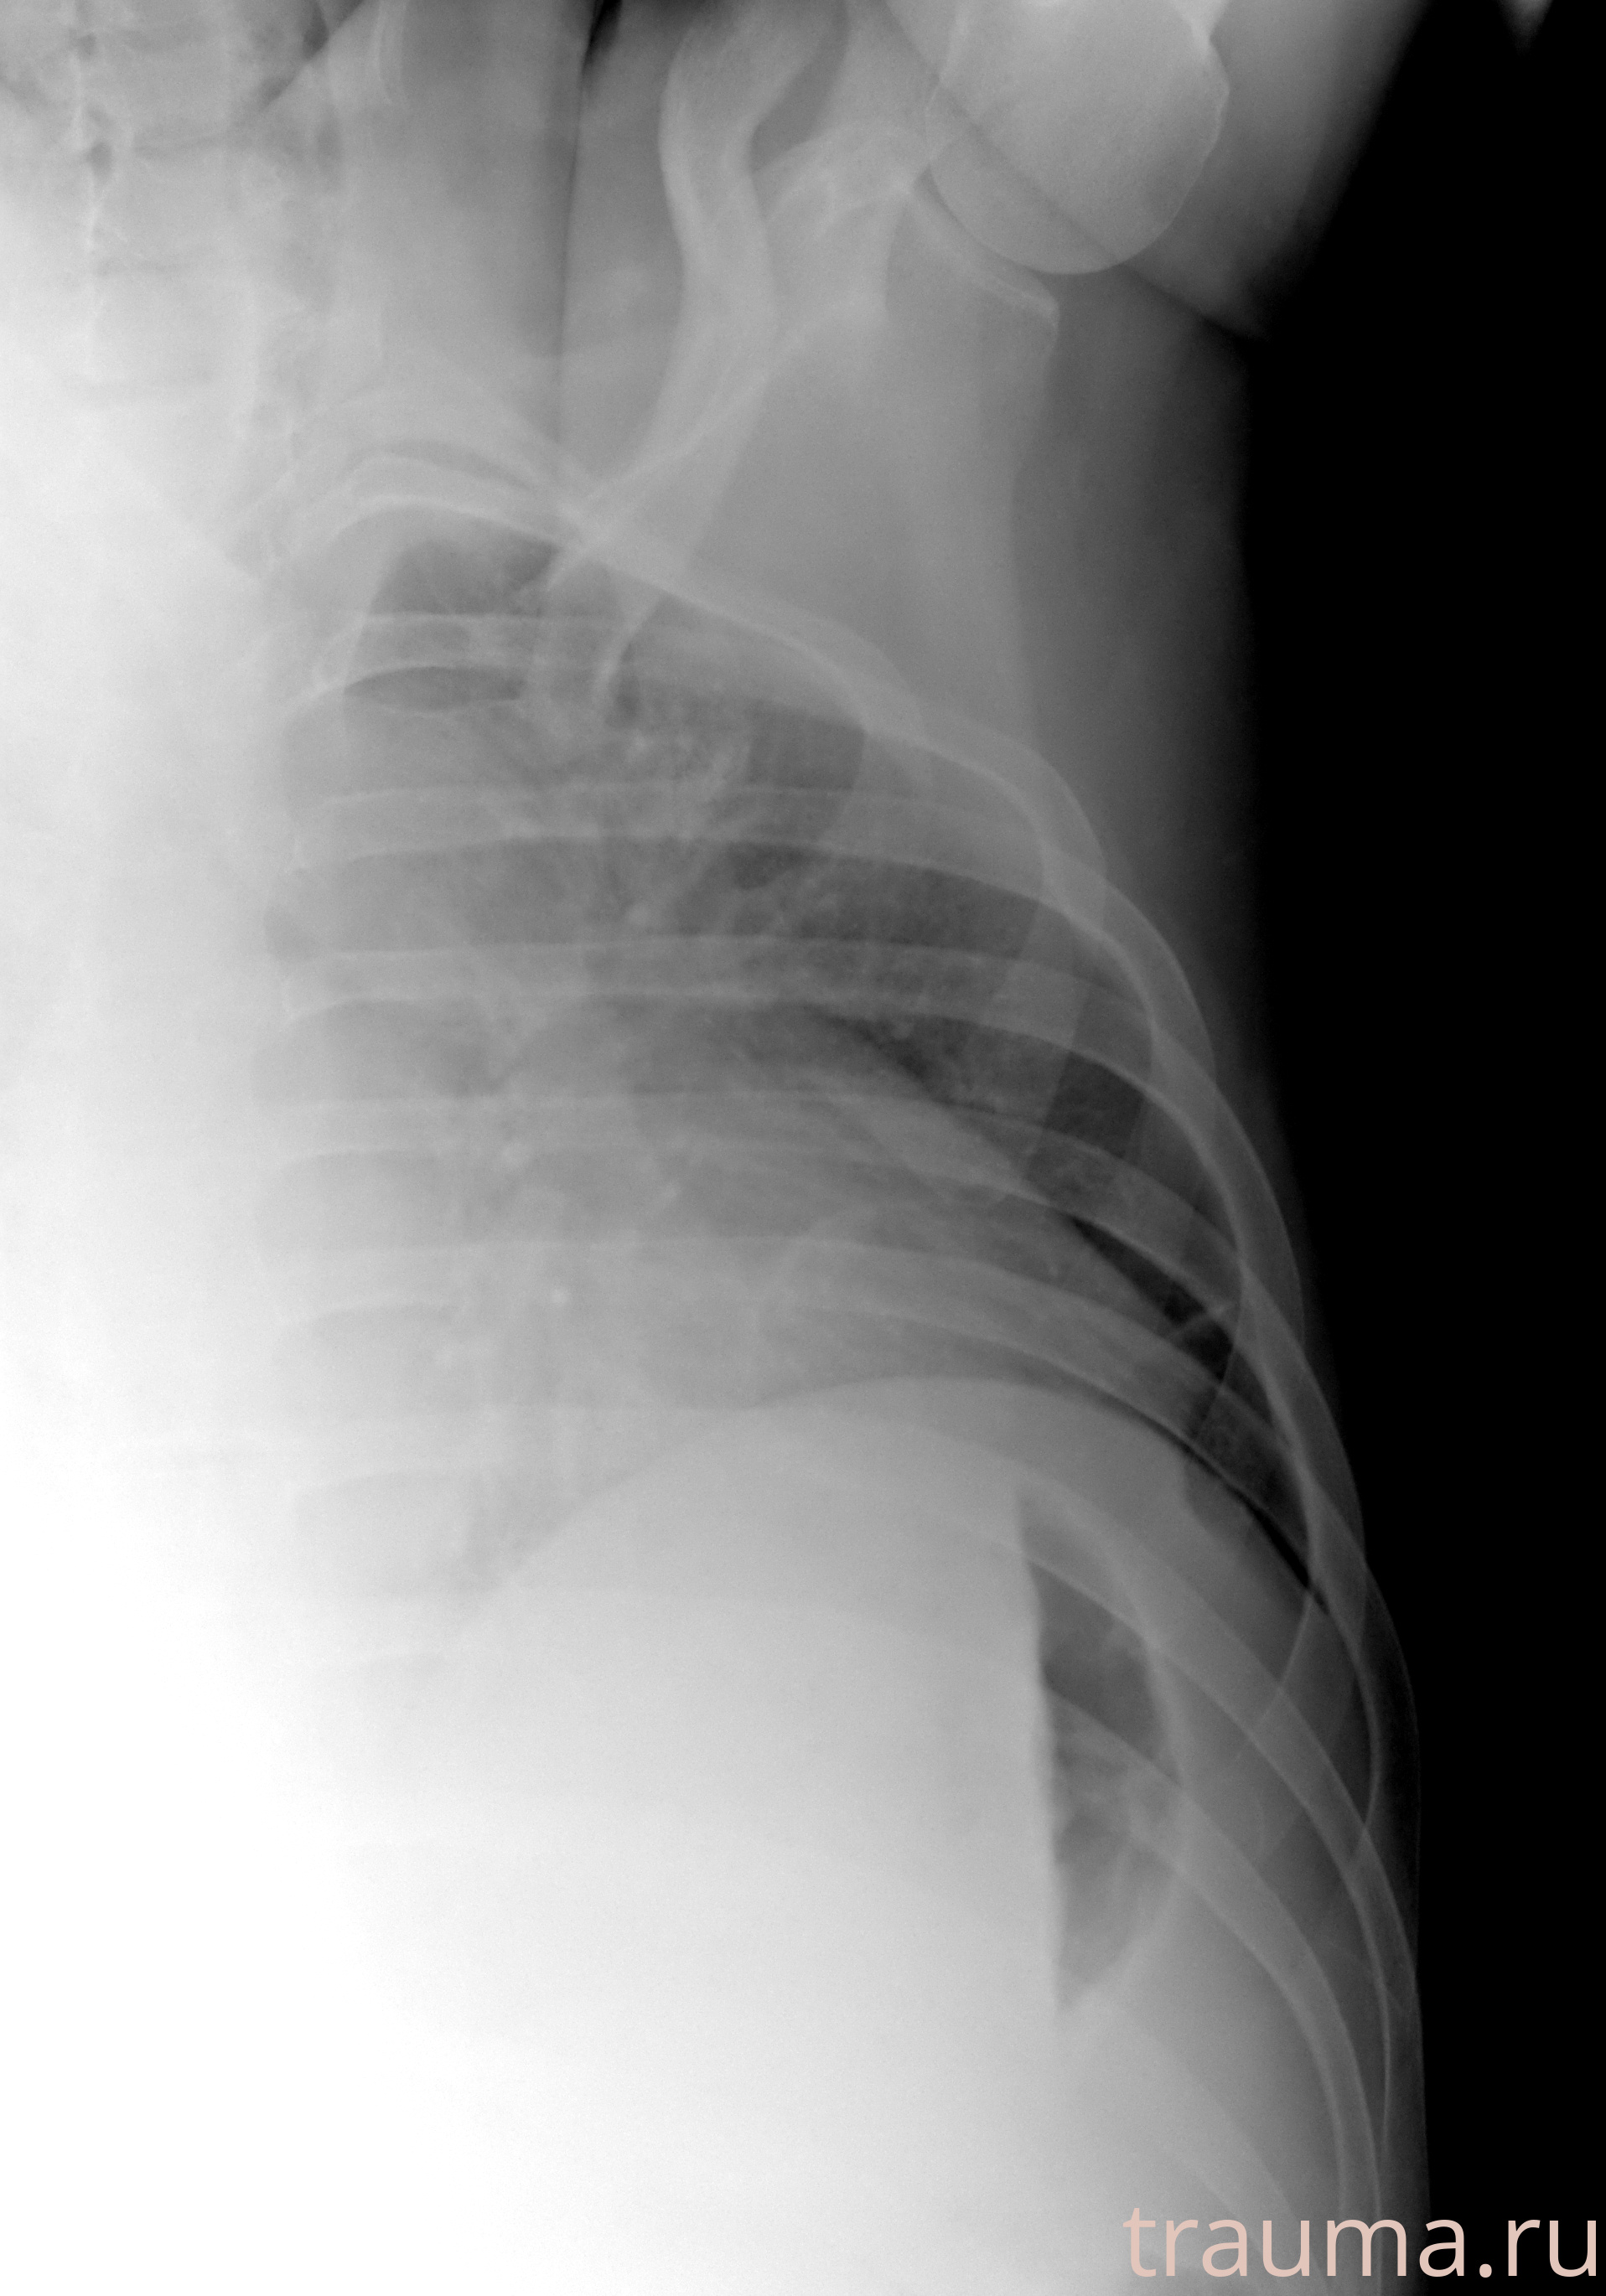

Рентгенограммы

Рентген на дому: по вашему адресу приезжает врач-рентгенолог, травматолог-ортопед с мобильным рентгеновским аппаратом, проводит диагностику травмы или заболевания, делает необходимые рентгенограммы, дает рекомендации по дальнейшему лечению. Получить качественные снимки в домашних условиях возможно благодаря уникальной методике, разработанной МосРентген Центром для института  Склифосовского

при переломе шейки бедра и пневмонии от компании МосРентген Центр - партнера Института имени Склифосовского